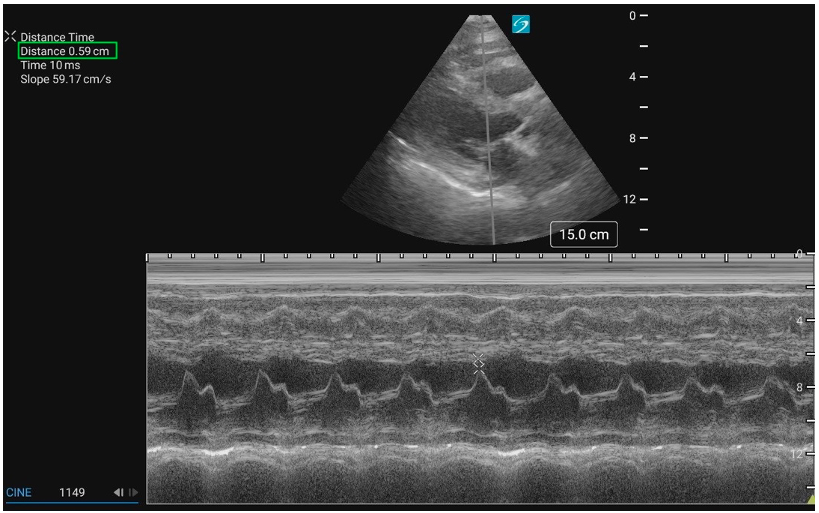

End Point Septal Separation

The EPSS is a measure of AMVL motion and is used as a way to semi-quantify LVfx. It refers to the minimal distance between the peak of the E-wave and the IVS at the same X-axis time point (figure 8).

Technique – EPSS

1. Activate M-mode and place the cursor line through the tip of the AMVL and the septum.

2. Measure EPSS if findings appear grossly abnormal, when a semi-quantitative baseline is useful for follow-up or clinical reassessment, or consultation with cardiology is anticipated.

· The EPSS is measured at the minimum distance between the AMVL and the septum in early diastole.

3. Save the M-mode image, and include the measurement if performed.

In a normally functioning LV, the E-point comes close to the septum (figure 9). In pediatric patients, there is limited validated evidence for normal EPSS values. A 1983 study provided guidelines for the use of EPSS in infants and children and found that normal EPSS was ≤ to 6mm, with 7-8mm being tail end of normal [21]. This was confirmed in a more recent study where an EPSS of 6.17 mm optimally distinguished normal from depressed LV systolic function, with a sensitivity of 86% and specificity of 92% [12].

The larger the EPSS distance the worse the function. Similar to the AMVL visual assessment, if the E-point is not close to the IVS during the M-mode tracing, this could suggest reduced systolic function. Specific cutoff values are available to guide interpretation (table 3) (Figure 10).

Figure 9: PLAX M-mode with normal EPSS measurement